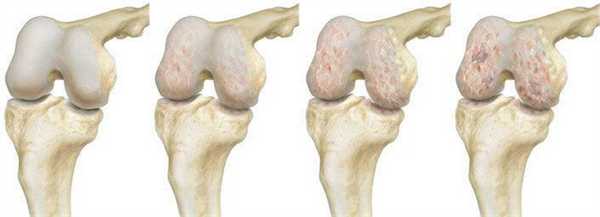

Костно-хрящевые структуры колена, приводящие в движение коленный сустав и отвечающие за опороспособность конечностей, - это самые уязвимые анатомические компоненты, которые поражаются артрозами. Эндопротезирование эффективный способом восстановления опорно-двигательного аппарата, которая подверглась серьезной дегенеративно-дистрофической агрессии на фоне хронического артроза.

Динамика разрушения хрящевой поверхности.

Полная замена коленного сустава

Проведение эндопротезирования считается крайней мерой, назначаемой при невозможности восстановления коленного сустава другими способами. Операцию выполняют чаще всего при артрите, артрозе, серьезных травмах.